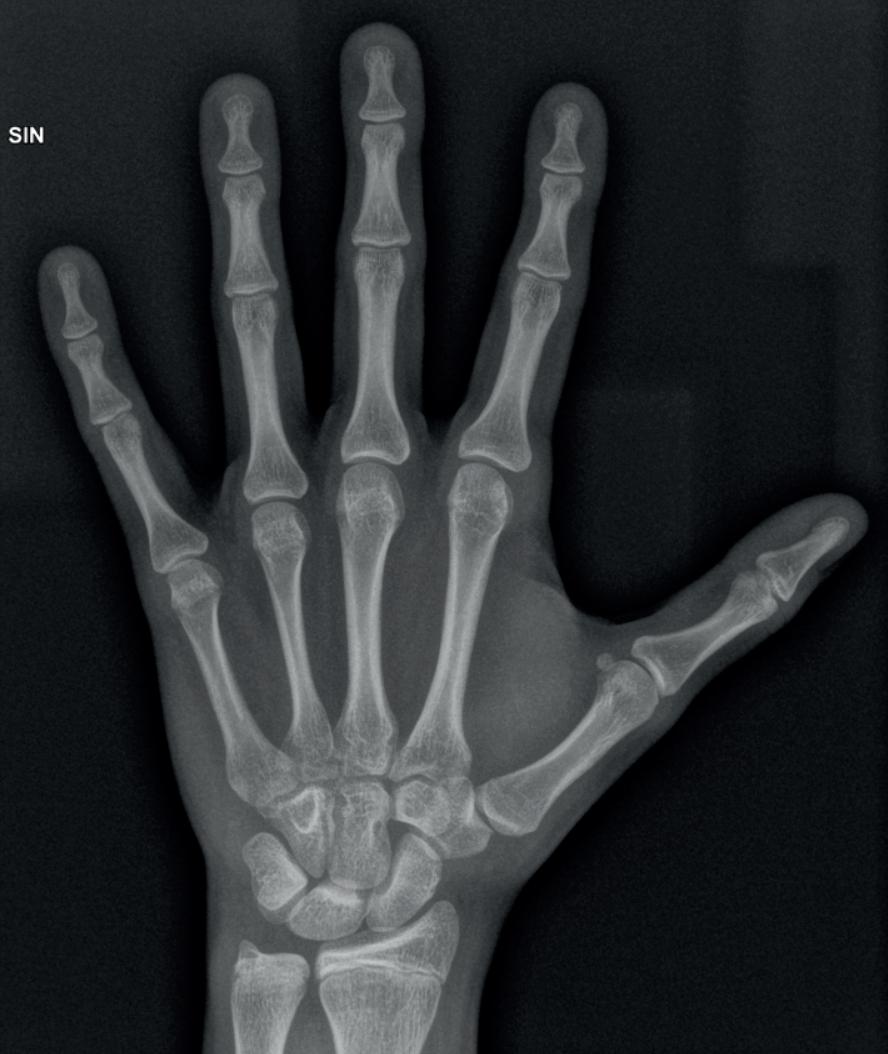

I Norge er røntgenundersøkelser av hånd og/ eller tann hyppigst brukt for medisinsk aldersbestemmelse. Metodene for fastsettelse av skjelettmodning ble utviklet til bruk på individer med kjent kronologisk alder i medisinsk sammenheng. Det er en klar korrelasjon mellom skjelett- og tannmodning og kronologisk alder. Problemet er at det er stor biologisk variasjon og at det er stor overlapp i modningsstadier mellom individer over og under 18 år. Tannmodning, og spesielt full håndmodning, skjer like rundt 18- års alder, og forblir så i samme utviklingsstadium livet ut. Det er derfor ikke mulig å si om en person med en fullt utviklet hånd er over eller under 18 år.

BioAlder - automatisert aldersprediksjon

I 2019 ble verktøyet BioAlder lansert. Verktøyet er basert på data fra over 22 000 individer i 34 vitenskapelige publikasjoner og benytter avanserte matematiske algoritmer. BioAlder lager en automatisert prediksjon av kronologisk alder basert på resultater fra røntgen av visdomstann og håndskjelett. Resultatet oppgis i henholdsvis 75% og 95% prediksjonsintervaller. I tillegg oppgir verktøyet andel individer under 16 og 18 år for de ulike modningsstadiene. BioAlder tar imidlertid ikke høyde for individuelle variasjoner i skjeletteller tannmodning, slik som medisinske tilstander, ernæring og genetikk. Videre er det ingen kombinasjon av hånd-og tannmodning som utelukker alder under 18 år. Verktøyet sier ingenting om hvor en saksbehandler skal plassere et individ innenfor hvert prediksjonsintervall.

Problematiske forutsetninger

Det unike med BioAlder er kombinasjonen av hånd og tannmodning som gir en noe større nøyaktighet i prediksjonsintervallet, gitt at hånd- og tannmodning er uavhengige data. Det er likevel ett grunnleggende problem; prediksjonsintervallene som legges til grunn for aldersbestemmelse forutsetter en kjent og jevn aldersfordeling av de som testes. Dette er jo et paradoks når alder er nøyaktig det vi ønsker å finne.

Dersom aldersfordelingen på de som undersøkes ikke er eksakt den som forutsettes (og det vil den jo i praksis ikke være), blir resultatene misvisende. Uansett hvor nøyaktig selve fastsettelsen av skjelett- og eller tannmodningen er, eller hvor representativ populasjon dataene er basert på, vil man aldri kunne angi aldersprediksjoner i en populasjon med ukjent alder.

Et annet vesentlig problem er at verktøyet åpner for bruk av bare én metode. De siste fire årene har kun tannrøntgen blitt

20 nr. 41 (1) 2023 Vindu mot verden

brukt til aldersbestemmelse. I oktober 2021 leverte det svenske Statens beredning för medicinsk och social utvärdering (SBU) en rapport om kronologisk aldersbestemmelse ved bruk av røntgenbestemt tannmodning og knemodning ved MR-undersøkelser. Denne konkluderte med at begge metodene er uegnet til dette formålet. Rapporten presiserte dessuten det universelle statistiske paradokset som gjelder alle medisinske aldersundersøkelser: «Det går inte att bedöma sensitiviteten, specificiteten, negativt prediktivt värde (NPV) eller positivt prediktivt värde (PPV) för någon av de två metoderna: MR-undersökning av tillväxtzonen i knät eller för röntgenundersökning av visdomständerna i underkäken, för att avgöra om en person av manligt respektive kvinnligt kön är över eller under 18 år. Detta då dessa parametrar är helt beroende på åldersfördelningen i den population som testas.»

World medical association (WMA) publiserte i 2019 en uttalelse om medisinsk aldersbestemmelse. WMA fastslår tydelig at dette kun skal utføres i eksepsjonelle tilfeller etter at alle andre ikke-medisinske metoder er forsøkt. Videre skal aldersfastsettelsen baseres på en totalvurdering. Dette er i tråd med norske bestemmelser. Vi vet likevel at UDI legger stor vekt på resultatene fra BioAlder.

WMA mener at medisinske undersøkelser som potensielt kan innebære risiko, eksempelvis bruk av røntgenstråler, ikke skal utføres annet enn i medisinsk sammenheng. Videre slås det fast at de individuelle resultatene av medisinsk aldersvurdering skal inneholde informasjon om nøyaktighet og reliabilitet av metodene, samt relevante feilmarginer. Hvordan skal dette etterleves når disse feilmarginene nettopp er avhengig av et individs kronologiske alder? Statistikken som brukes er relativt komplisert å forstå, og det vil være vanskelig både for en saksbehandler og for individet som testes å sette seg inn i de statistiske forutsetningene som

ligger til grunn for sannsynlighetsvurderingene (dvs. aldersprediksjonen) ved medisinsk aldersvurdering.

En ærligere måte å fremstille data på er kanskje å si noe om en feilmargin per alder; nemlig hvor stor andel av for eksempel 16- og 17- åringer som vil bli klassifisert som voksne og hvor stor andel av 18- og 19-åringer vil bli klassifisert som barn ved bruk av ulike medisinske aldersbestemmelsesmetoder. Datagrunnlaget for BioAlder viser at i underkant av 30 % av 17- årige og ca. 7% av 16-årige gutter har en helt ferdig utviklet håndrot (skjelettalder 19 år) og vil ikke radiologisk kunne skilles fra en 18-åring med moden håndrot eller en 80-åring. Over 50% av 17-årige og ca. 20% av 16-årige gutter har skjelettalder over 18 år. Ved å illustrere hvordan utviklingsstadiene, eller kombinasjonen av disse, fordeler seg i ulike aldersgrupper vil myndighetene i hvert fall ta stilling til «smertegrensen» for hvilken retts(u) sikkerhet man utsetter individer i ulike aldersgrupper for.